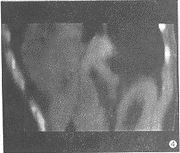

4例矢状位重建图像,均显示左膈后份变平直呈水平状,后肋膈角变浅,膈肌食管裂孔增宽(图4)。

图4 同一病例CT矢状位重组图像示食管裂孔增大,膈肌后份变平